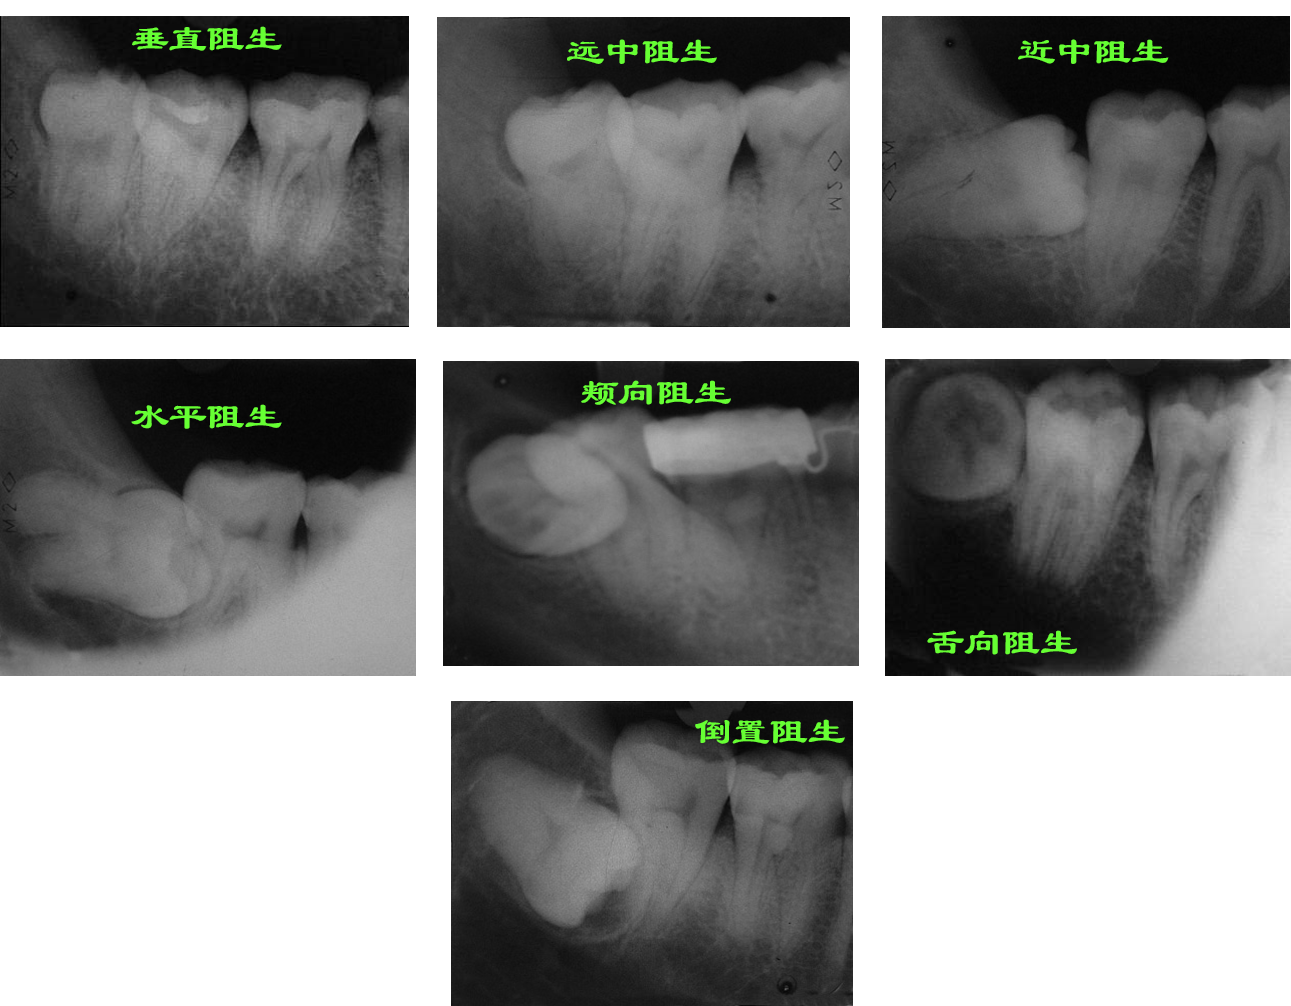

大家好,我是臺灣健康欄目的總編輯。今天我們將為大家揭秘長智齒痛的快速舒緩法,讓你輕鬆應對口腔不適!相信對許多人來說,智齒問題都是一大煩惱,但別擔心,我們有秘訣來幫助你緩解痛苦。